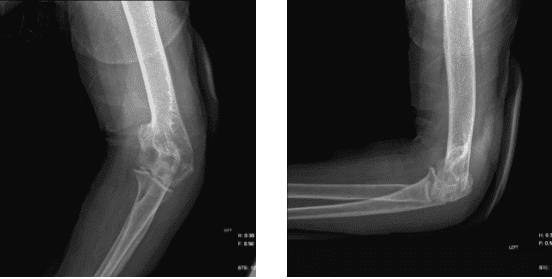

A 74 year-old female patient is here with X-rays of her left elbow and complains the pain from her elbow. According to her X-ray she has Olecranon TBW with increased temperature and redness. However, we discussed the Risks, benefits and alternatives at length.

Left elbow X-ray